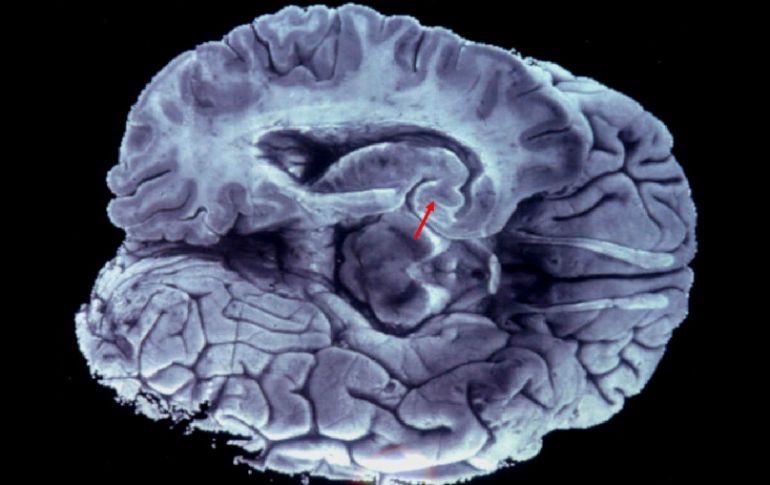

Tecnología | Existe una correlación entre el cociente de encefalización y el riesgo de extinción Tener un cerebro grande no es necesariamente una buena noticia: estudio Existe una correlación entre el cociente de encefalización y el riesgo de extinción Por: AFP 16 de febrero de 2016 - 20:21 hs Señalan que mantener un cerebro grande tiene un coste metabólico significativo. EFE / ARCHIVO PARÍS, FRANCIA (16/FEB/2016).- Ya se sabía que tener un cerebro grande no es necesariamente una garantía de inteligencia, pero de acuerdo a un estudio publicado el miércoles en la revista Proceedings B de la Royal Society británica, podría estar relacionado con una mayor probabilidad de extinción. Tener un cerebro grande podría ser una desventaja, afirma el profesor Eric Abelson, del departamento de biología de la Universidad de Stanford, Estados Unidos. Este investigador calculó la talla del cerebro de mil 679 animales (de 160 especies diferentes) y comparó estas medidas con los datos de la Unión internacional para la conservación de la naturaleza, que evalúa el riesgo de extinción de miles de especies y subespecies. Así, puso en evidencia una correlación entre el cociente de encefalización (que mide la talla del cerebro en relación al resto del cuerpo) y el riesgo de extinción. Esta correlación es aún más grande en los animales pequeños, afirma. En efecto, mantener un cerebro grande tiene un coste metabólico significativo. Implica un consumo de energía más importante sin que, al parecer, esto implique mayores capacidades de adaptación. Y para Eric Abelson, los costes de un fuerte cociente de encefalización superan las ventajas en las especies pequeñas Temas Investigación científica Ciencia médica Estudios Cerebro Lee También Estudio chino revela una mutación que eleva riesgo de alzhéimer ¿Cómo se forman los recuerdos en la mente? La tendencia a hacer ejercicio se trasmite de padres a hijos y esta es la explicación de la ciencia Esto dijo Israel sobre la extradición de Zerón a México Recibe las últimas noticias en tu e-mail Todo lo que necesitas saber para comenzar tu día Registrarse implica aceptar los Términos y Condiciones